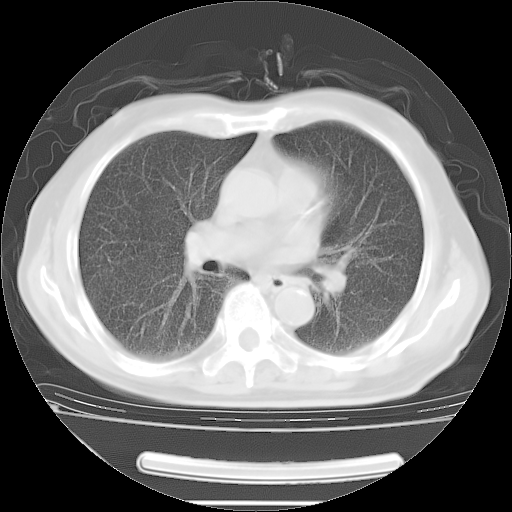

今天复查肺部CT,发现双肺广泛磨玻璃样改变。所以我把3月19日和5月9日相隔50天的肺部CT上传。请大家会诊。

5月9日肺部CT(在4月27日齐鲁医院肺部CT描述部分肺组织磨玻璃样改变,12天后肺组织广泛磨玻璃样改变)

大致读了系列胸部CT:纵隔窗无明显异常,肺窗:从4、27至今:主要是双肺中下野外带可见毛玻璃样改变,目前处于急性肺泡炎阶段,至于原因考虑1、结替组织或胶原血管性疾病所致?2、恶性疾病如恶组在肺部所致的表现或细支气管肺泡癌?3、药物或其它原因如肺蛋白沉着症所致肺泡炎目前不太可能?总之,明天就去请我院的呼吸科、感染科、血液科和临免专家会诊哈。